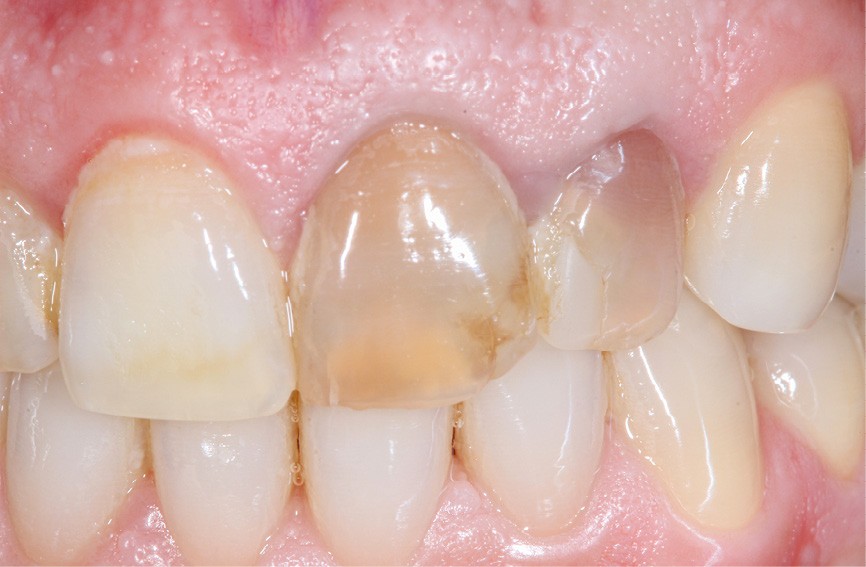

– Traumatismes (fig. 5a, b).